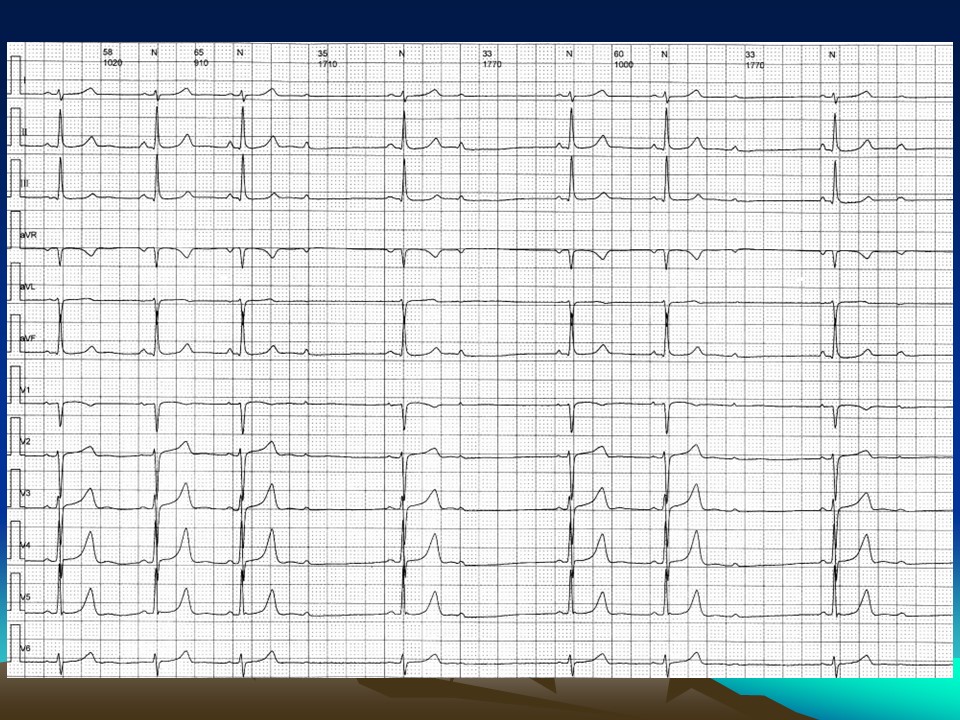

“心电图常见图形及诊断PPT” 的相关文章